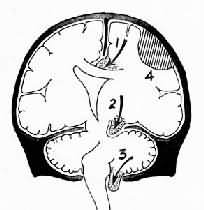

图16-6 脑疝模式图

1.扣带回疝;2.海马钩回疝;3.小脑扁桃体疝;4.硬膜外血肿